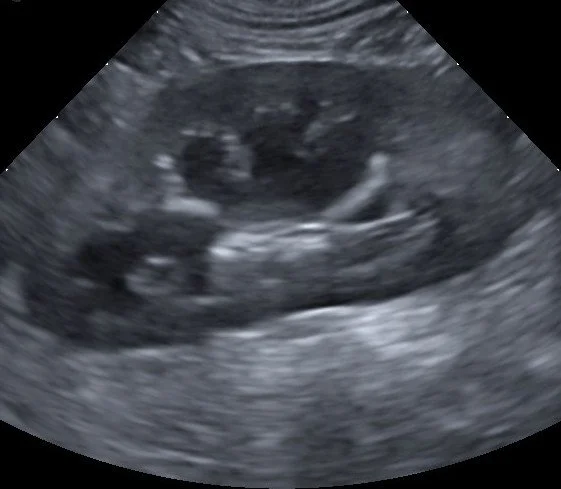

• Abnormal bloodwork?

Equivocal Radiographs?

Suspect an Endocrine disease/disorder?

Is this a surgical or medical case?

A full abdominal ultrasound can help answer these questions and many more!

• Real or false pregnancy?

Hypercalcemia?

Palpable thyroid mass?

Ultrasound can be used on many areas of the body, not just the abdomen, to aid diagnosis and tissue sampling.